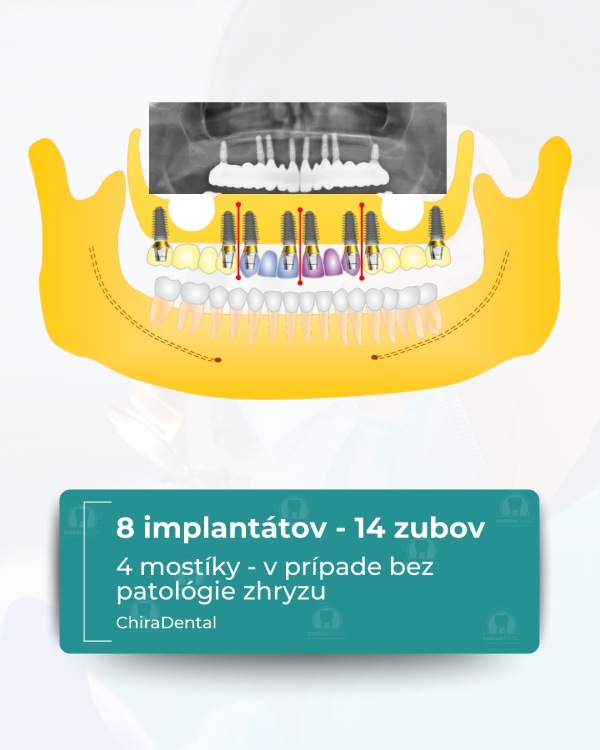

Moderné technológie umožňujú rýchlo, spoľahlivo a esteticky obnoviť celú čeľusť, a to aj v zložitých prípadoch. Ponúkame niekoľko kompletných rehabilitačných systémov založených na počte implantátov a úrovni fixácie budúcej štruktúry. Možnosť 1 - All-on-4 (Základné riešenie) Táto metóda je vhodná pre pacientov so zníženým objemom kosti alebo pre tých, ktorí chcú nové zuby čo najrýchlejšie. Čo robíme: Inštalujeme 4 implantáty do hornej alebo dolnej čeľuste; V prípade potreby vykonáme augmentáciu kosti a plastiku ďasien počas tej istej návštevy; Nasledujúci deň odoberieme odtlačky pre dočasnú štruktúru; Po 3-5 pracovných dňoch pacient dostane dočasné kovovo-akrylátové zuby na dlhodobé nosenie. Výsledok: približne 10 nových zubov, ktoré umožňujú pohodlné žuvanie a úsmev. Po 3-6 mesiacoch vykonávame trvalé rekonštrukcie s použitím kovovo-keramiky alebo zirkónu. ⭐ Možnosť 2 — All-on-6 (štandardné riešenie) Optimálna možnosť pre pacientov, ktorí vyžadujú väčšiu stabilitu a väčšiu žuvaciu záťaž. Čo robíme: Inštalácia 6 implantátov so súčasnou augmentáciou kosti a ďasien; Odtlačky sa robia nasledujúci deň;Dočasné kovovo-akrylátové korunky sa inštalujú po 3-5 dňoch.

Výsledok: kompletný oblúk 14 zubov. Definitívna rekonštrukcia (kovovo-keramika alebo zirkón) sa vykonáva po 3-6 mesiacoch.